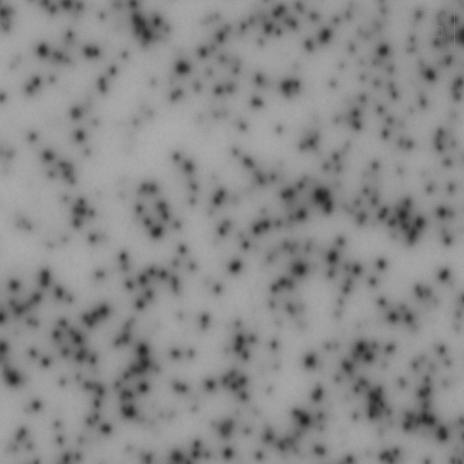

精確斑點定位

基于RAWSpot技術的精準定位,可以準確獲得斑點位置及對應細胞的分泌類型。

ELISpot斑點中心定位